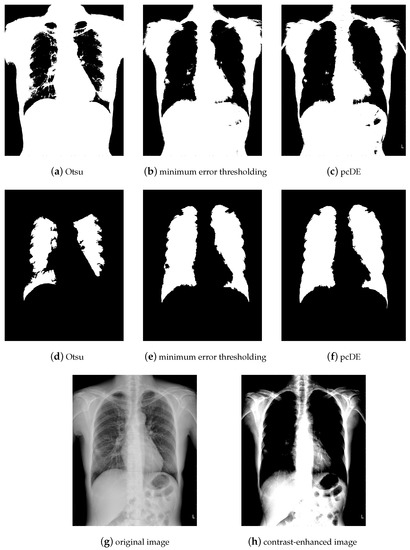

- Image preprocessing. Enhance the contrast of the image to achieve better segmentation.

- Calculate the optimal threshold for image segmentation through different methods to get the binarized image.

- Use morphological methods to process images to extract targets.

- Mark target contour.

- : Represent the result of ground truth segmentation (Figure 13).

- : Represent the result of algorithm segmentation.